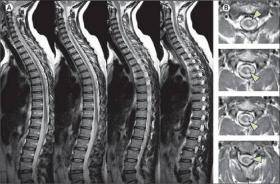

Thoát vị đĩa đệm là một trong những căn bệnh xương khớp phổ biến hiện nay gây ảnh hưởng lớn đến sức khỏe, cuộc sống sinh hoạt của người bệnh. Không những thế, thoát vị đĩa đệm nếu để lâu...